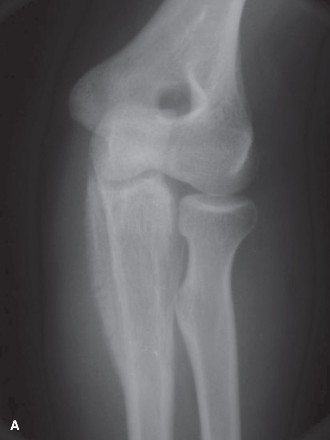

1. Plain Radiographs (AP/Lateral): Initial assessment of the lesion, cortical integrity, and overall bone architecture. Used for Mirel score size and character assessment.

2. Computed Tomography (CT) Scan: Provides detailed information on cortical destruction, medullary canal involvement, soft tissue extension, and precise lesion dimensions. Crucial for planning implant length and diameter, and for assessing the extent of lytic defects requiring augmentation.